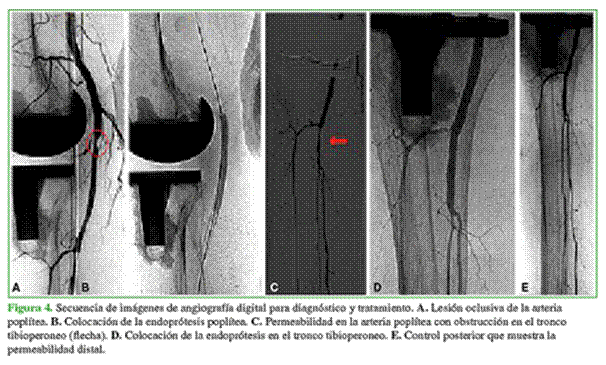

La paciente continuó con una regular evolución, sin un diagnóstico certero. El día 14 se realizó otra ecografía Doppler, en esta oportunidad arterial y venosa, y se diagnosticó una oclusión parcial de la arteria poplítea y del tronco tibioperoneo. Se solicitó una angiografía para completar la evaluación e indicar un posible tratamiento.

Como se muestra en la Figura 4, la arteria poplítea tenía una oclusión parcial de su tercio medio y distal con recanalización en el tronco tibioperoneo que presentaba una estenosis severa difusa. La arteria tibial anterior estaba permeable hasta el tercio distal donde se ocluía, las arterias peronea y tibial posterior estaban permeables.

Se colocó una endoprótesis Complete® SE (Medtronic Inc., Santa Rosa, CA, EE.UU.) de 5 x 80 mm con la cual se cubrió la lesión oclusiva de la arteria poplítea para posteriormente realizar una angioplastia por la lesión residual crónica. En el control posterior, se observó una arteria poplítea permeable sin áreas de estenosis residual significativa y persistencia de la lesión del tronco que fue tratada con una endoprótesis Resolute Integrity® (Medtronic Inc., Santa Rosa, CA, EE.UU.) de 3,5 x 30 mm; se logró un buen resultado angiográfico final, sin evidencia de estenosis residual.

La paciente evolucionó de manera favorable y el dolor mejoró. En el control anual posoperatorio, la movilidad de la rodilla era de 0-115°. El puntaje de dolor, según la escala analógica visual, era de 2/10 y tenía un puntaje de 85/90 en el Knee Society Score. No hubo complicaciones de la lesión vascular. Se realizó una ecografía Doppler arterial de control que reveló que las dos endoprótesis colocadas (poplítea y tronco tibioperoneo) estaban permeables, con flujo bifásico a velocidades conservadas.